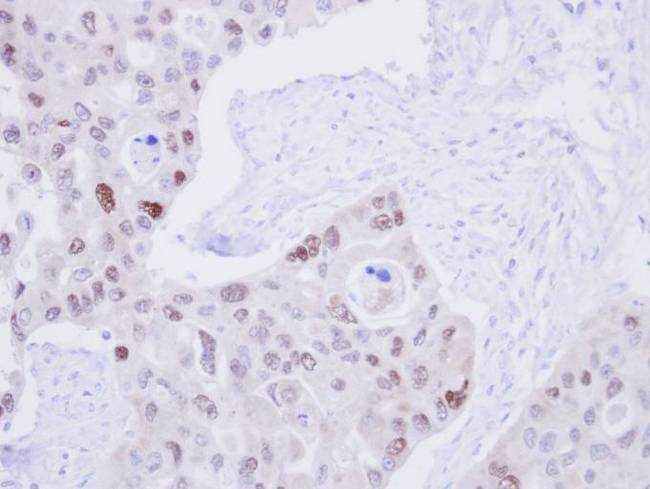

- IHC of paraffin-embedded H441 Xenograft using DNA ligase 3 antibody at 1:100 dilution.